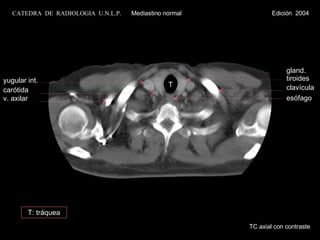

yugular int. carótida  v. axilar gland. tiroides T clavícula esófago TC axial con contraste CATEDRA  DE  RADIOLOGIA  U.N.L.P.   Mediastino normal  Edición  2004 T: tráquea